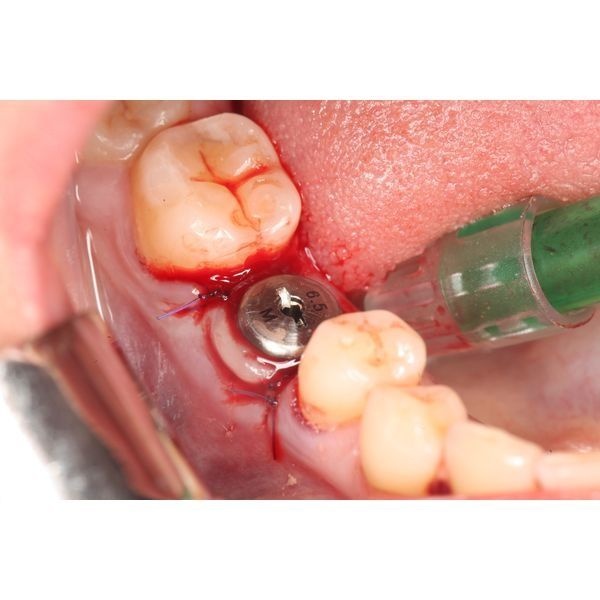

- наложили рассасывающиеся швы и обработали операционную рану;

- провели рентген-контроль.

Весь приём длился 45–60 минут.